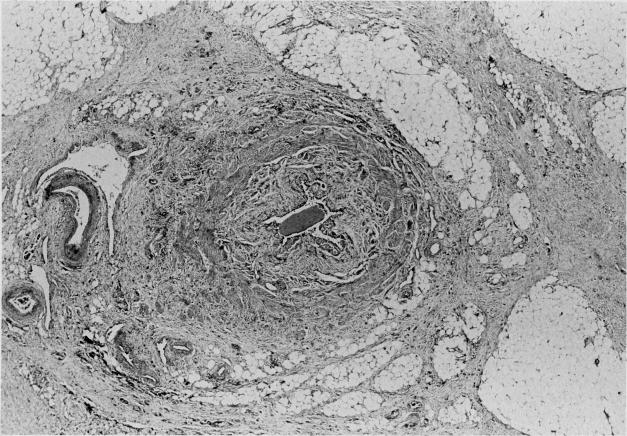

Retroperitoneal fibrosis secondary to carcinoma of the gallbladder has not been reported previously. Such a combination is reported and a review of the pertinent literature presented.